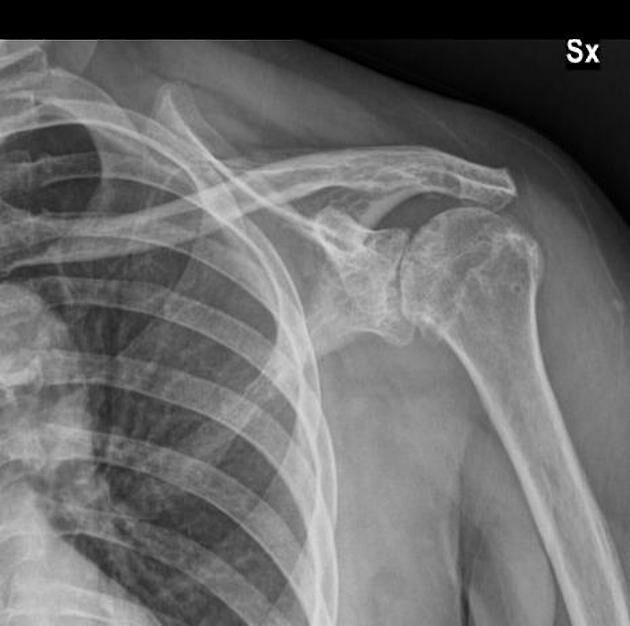

- Q1

What does this Shoulder XR Show?

Bankart Fracture

Proximal Humerus Fracture

Rotator Cuff Arthropathy

Shoulder Osteoarthritis

ACJ Osteoarthritis